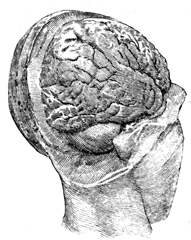

Chapter II—Structure of the Brain.

Man a triple being—Materialists and illusionists misconceive him—Relation

of the soul to the brain and body—The nervous system;

illustration—Embryonic condition—Anatomical descriptions unsatisfactory

and the phrenological school incorrect—Exterior view

of the brain in the head, illustrated and described—The cerebrum,

cerebellum, and tentorium—Interior view of the base of the skull—Bones

of the head illustrated—Division of the brain into lobes

and convolutions, with illustration—Frontal, middle, parietal,

tempero-sphenoidal, and occipital—Anatomical plan or grouping of

convolutions differs from their actual appearance—View of the superior

surface illustrated—Difference between the irregular convolutions

and the angular maps—View of the inferior surface of the

brain—Illustration and description of the parts—Interior view of

section on the median line—Divided and undivided surfaces-Corpus

callosum explained—The two brains and their diagonal

relations to the body—Penetrating and describing the lateral

ventricles—The serum in the brain—Variations of serum and

blood—Variations in hydrocephalus and insanity—Our power to

modify the brain and change our destiny—Power of education—Responsibility

of society—The lateral ventricles the centre of the

brain—Base of the ventricles, the great inferior ganglia of the

brain, corpora striata, and thalami—Their radiating fibres inclosing

a cavity—The thalami and their commissure and third ventricle—The

medulla oblongata, cerebellum, and arbor vitæ—The pons

Varolii and crura of the brain—the corpora quadrigemina, pineal

gland, fourth ventricle, and calamus scriptorius.